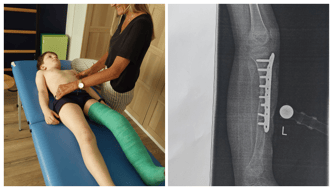

Minęło pięć miesięcy od zdjęcia aparatu, a zrost kości nie tylko postępuje bardzo wolno, to jeszcze jest na tyle słaby, że operowana piszczel odkształca się pomimo stabilizacji gipsem – nawet oko laika zobaczy, że kość na zdjęciu RTG wygląda bardzo źle.

Lekarze zadecydowali o pilnej konieczności przeprowadzenia operacji, dzięki której zabezpieczą słabą kość metalową płytką.

Płytka w kości jest stabilna, więc 7 czerwca kontrolne RTG i jeżeli wszystko będzie w porządku 17 czerwca 2024 mamy stawić się w klinice, aby rozpocząć robienie upragnionych ortez.